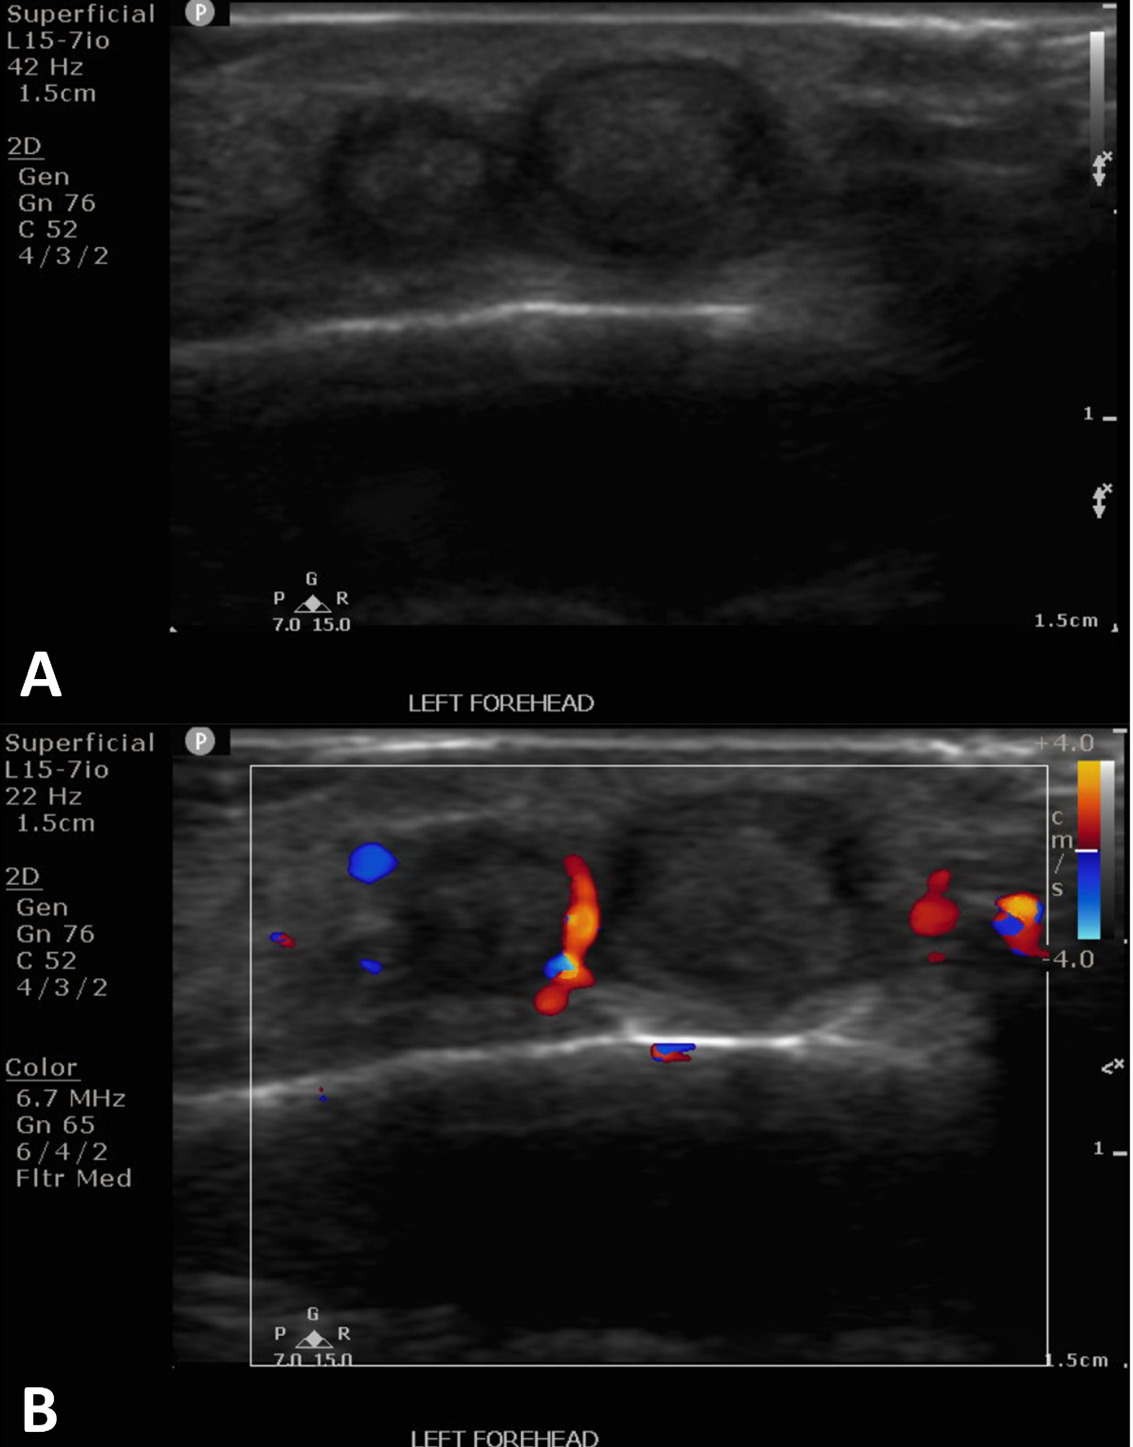

The patient is a 25-year-old male who was struck by a paintball in the left frontotemporal region, initially causing bleeding and ecchymosis. Two months later, he presented to an outpatient vascular clinic due to the development of a pulsatile mass of the left forehead (Figure 1). The clinical finding prompted a diagnostic US including arterial duplex evaluation of the site which confirmed tandem pseudoaneurysms in the scalp left of midline arising from the parent left superficial temporal artery (Figure 2).

After discussion and counseling regarding the treatment options, the patient elected to have the percutaneous procedure performed in lieu of surgery as his initial choice of treatment. The patient emphasized understanding that a surgical excision may be required in the future for complete cosmetic and symptomatic resolution. Two weeks after the ultrasound study was conducted, the pseudoaneurysms were treated with direct, percutaneous pseudoaneurysm needle access and subsequent angiogram and n-BCA glue embolization. Specific procedure details include: the procedure was performed under moderate sedation with IV administration of midazolam and fentanyl. The forehead was prepped and draped in sterile fashion and subcutaneous injection of 1% lidocaine was used for local anesthesia. Then, the pseudoaneurysm was percutaneously accessed with a 21-gauge needle under direct US guidance. Angiography through the needle demonstrated successful access to the pseudoaneurysm; which was located at a branch point of the STA. Further angiographic opacification of the vascular territory demonstrated two additional small pseuaneurysms, one arising from each branch (Figure 3).